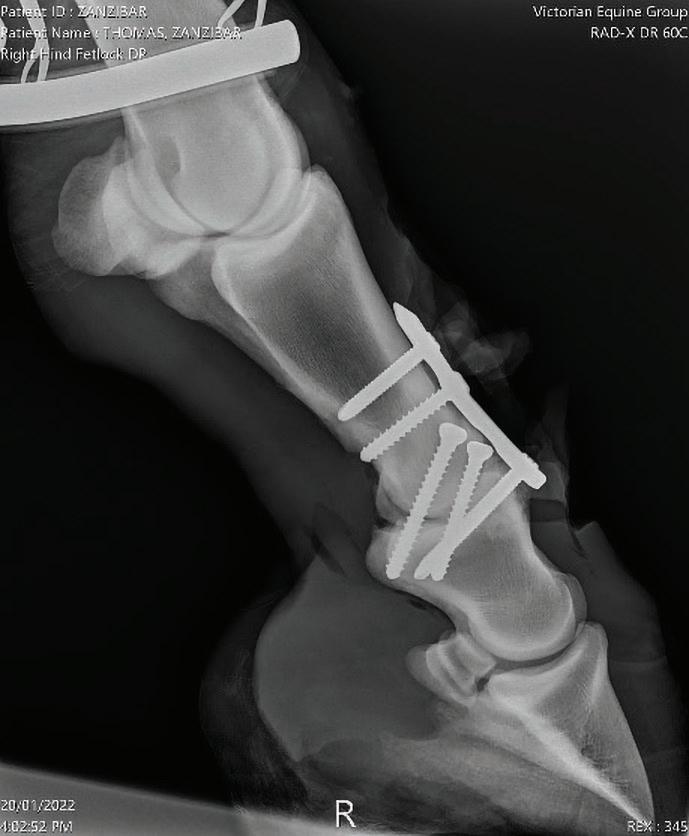

Case Report – Proximal interphalangeal (PIP) joint arthrodesis in a warmblood

32